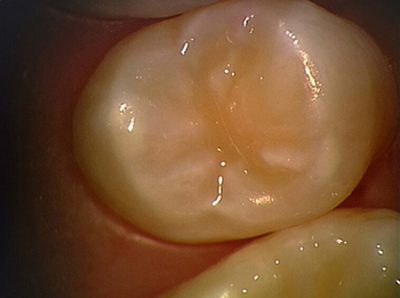

Erweiterte Fissurenversiegelung und Mikrofüllung

nach Fertigstellung